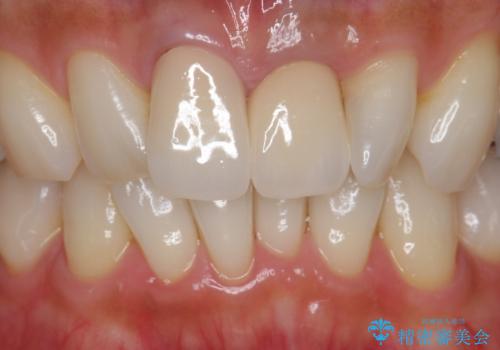

歯をある程度削ることにはなりますが、被せ物にすることで歯の変色を隠し短期間でキレイな口元に仕上げることができました。

前歯の色・形・ガタつきともに改善することができ、大変喜んでいただけました。